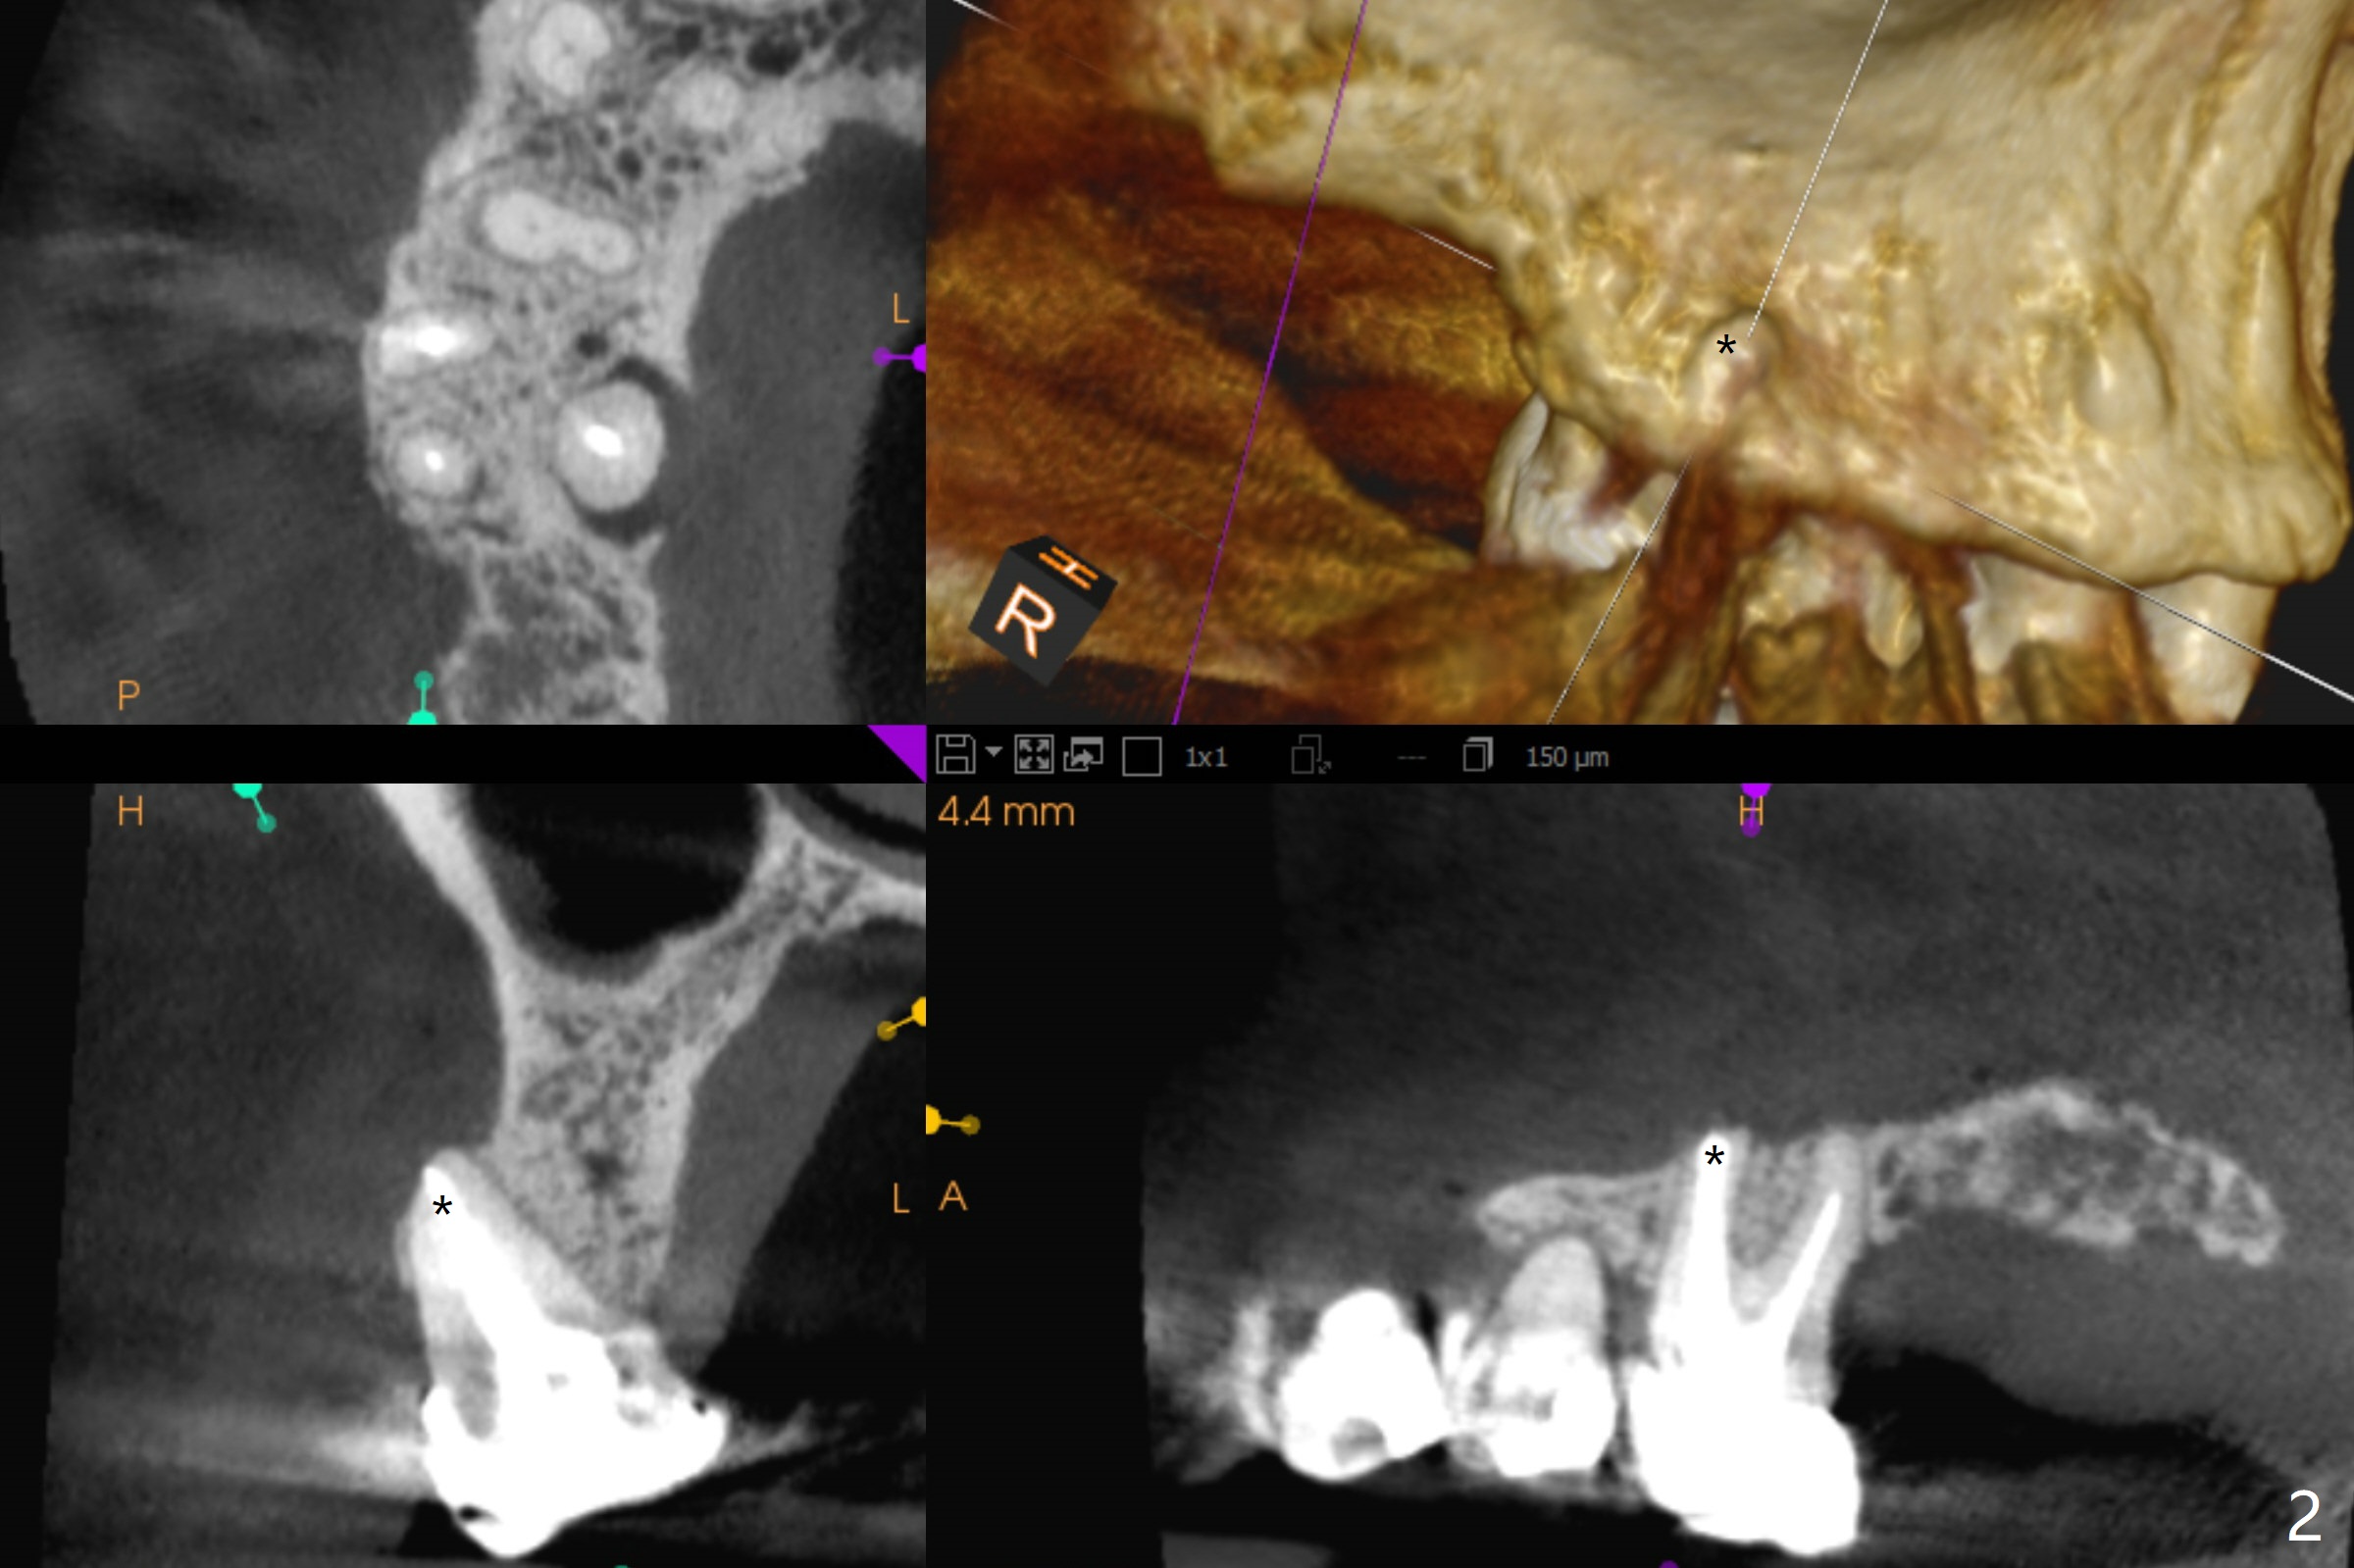

A 52-year-old woman has had chronic abscess associated with the tooth #3. The palatal root is exposed (Fig.1 P), suggesting root fracture. The apex of the mesiobuccal root seems to stick out of the buccal plate (Fig.2 *). The root canal filling is incomplete in the distobuccal root (Fig.3 *). The tooth appears to have guarded prognosis. Extraction and immediate implant is apparently a better option (Fig.4,5). It would be safer to start osteotomy in the middle of the remaining septum (Fig.6, as compared to Fig.5). After sinus lift with PRF membrane (Fig.7 yellow curved line) and implant placement (green), another piece of PRF membrane will be placed against the palatal wall of the socket, followed by bone graft (red circles) and a 25-degree angled abutment (pink).